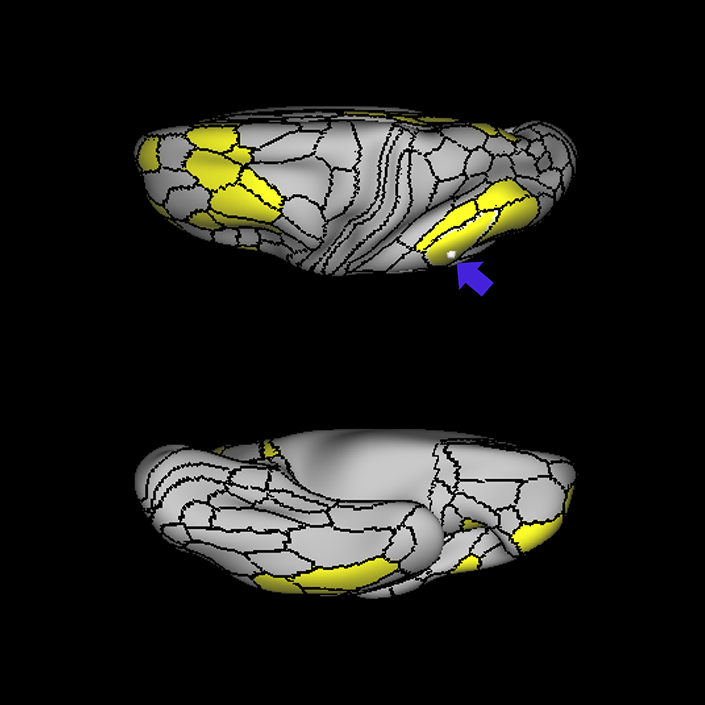

ᐅ SummaryArea 45: part of the inferior frontal gyrus of the lateral frontal lobe. In addition to its known association with Broca's area, is sometimes represented as part of Broca's complex ᐅ Where is it?Area 45 is the lateral surface of pars triangularis of the IFG. ᐅ What are its borders?Area 45 borders area 47L anteriorly and area 44 posteriorly. Its superior edge borders area p47r, IFSa, and IFSp. Its opercular surface is conveniently named FOP5 ᐅ What are its functional connections?Area 45 demonstrates functional connectivity to areas SFL, IFSp, 44, a47r, 47s, 47L, 9a, 9p, 9m, 8AV, and 8BL in the dorsolateral frontal lobe, area 8BM in the medial frontal lobe, area 55b in the premotor areas, areas FOP5, and PSL in the insula-opercular region, areas TGd, TGv, TE1a, STSva, STSdp and STSvp in the temporal lobe, area PGi in the inferior parietal lobe, and area 31pd in the medial parietal lobe. ᐅ What are its white matter connections?Area 45 is structurally connected to the arcuate/SLF and IFOF. However, arcuate/SLF connections are not consistent across individuals. Connections with the arcuate/SLF project posteriorly and wrap around the Sylvian fissure to the middle temporal gyrus to end at TE1p. There are also projections from the arcuate/SLF before it terminates to parcellations A4 and PBelt. IFOF connections travel from 45 through the extreme/external capsule and continue posteriorly through the temporal lobe to end at occipital lobe parcellations V1, V2, V3 and V4. Local short association bundles connect with 44 and FOP4. ᐅ What is known about its function?Area 45, in addition to its known association with Broca's area, is sometimes represented as part of "Broca's complex", including Brodmann Areas 45, 46, 47 and the mesial supplementary motor area of 6, which contribute to a frontal-subcortical circuit. |

A: lateral-medial

B: anterior-posterior

C: superior-inferior

DTI image |